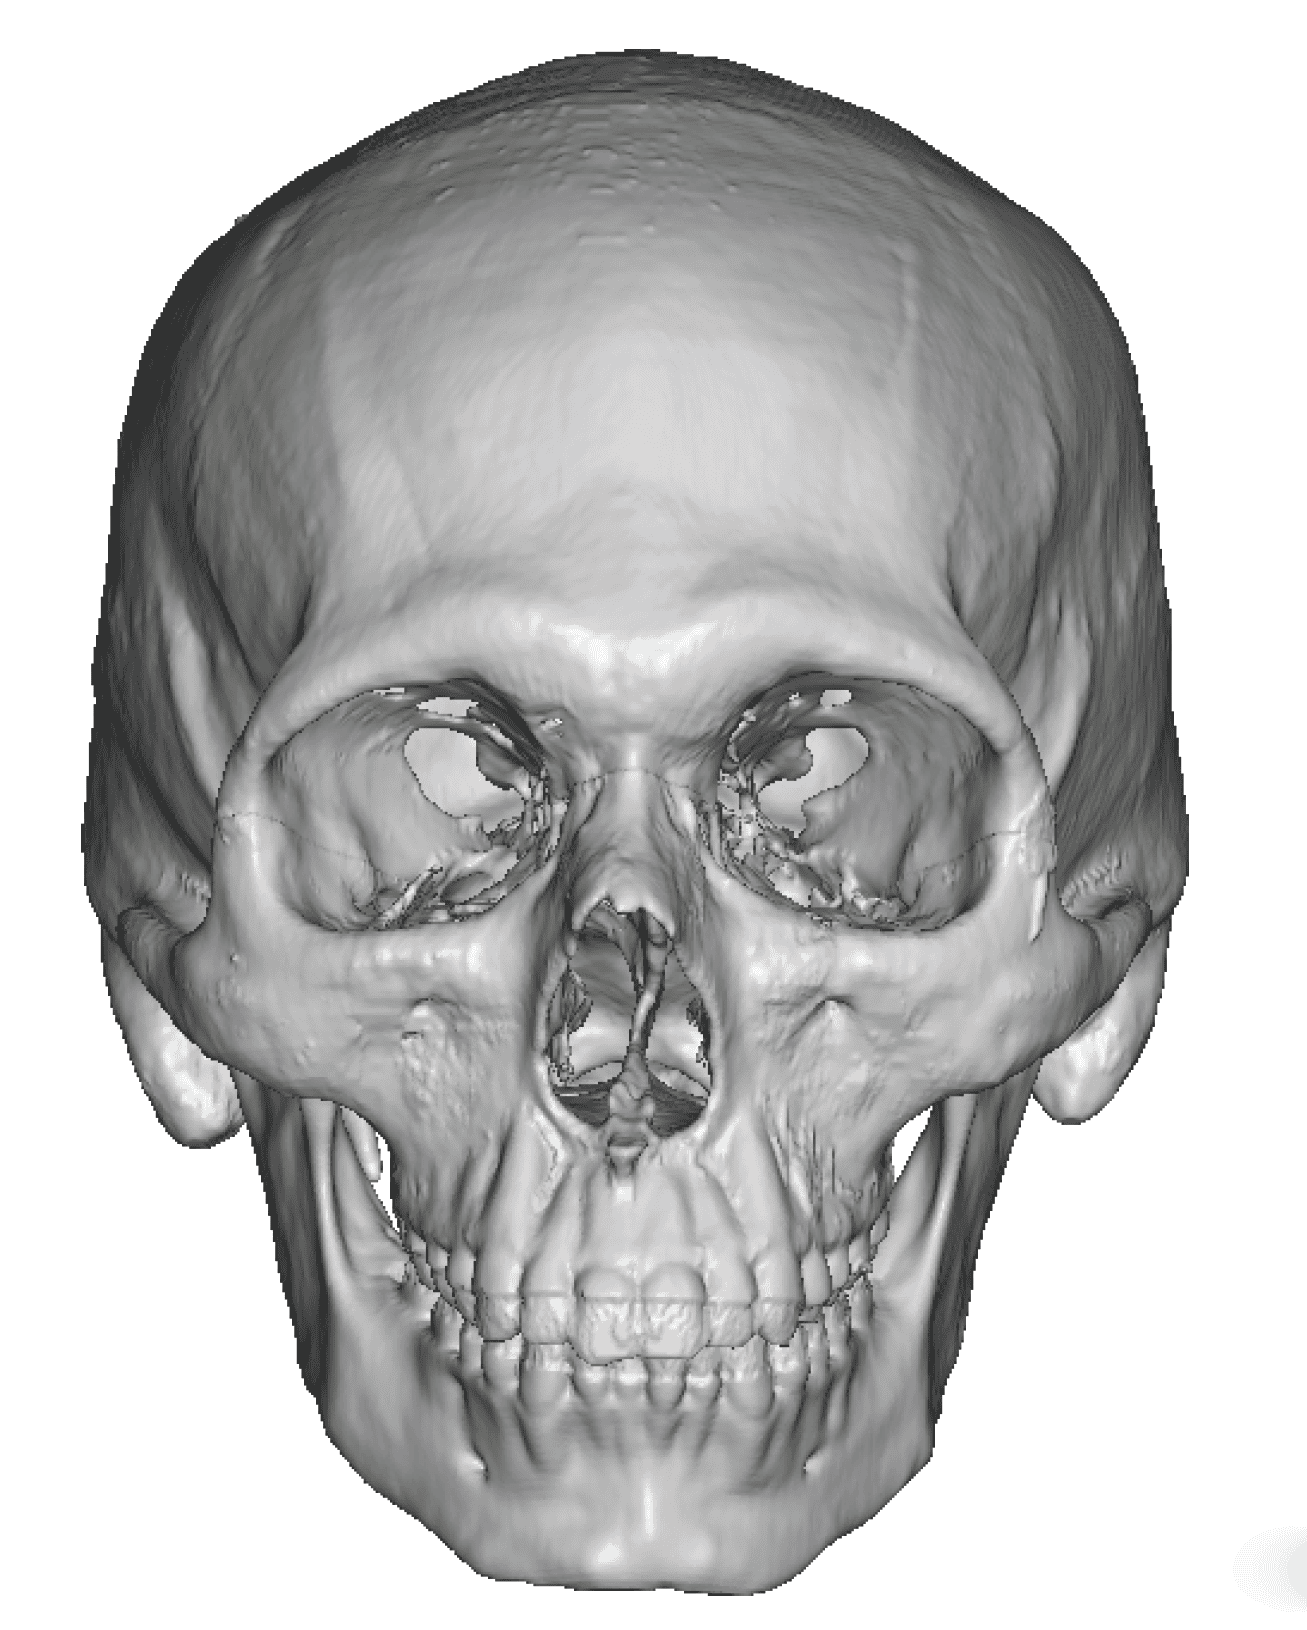

Patient 27

Desire for reduction of skull ridge reduction.

Anterior sagittal skull ridge reduction by bone burring.

Desire for reduction of skull ridge reduction.

Anterior sagittal skull ridge reduction by bone burring.